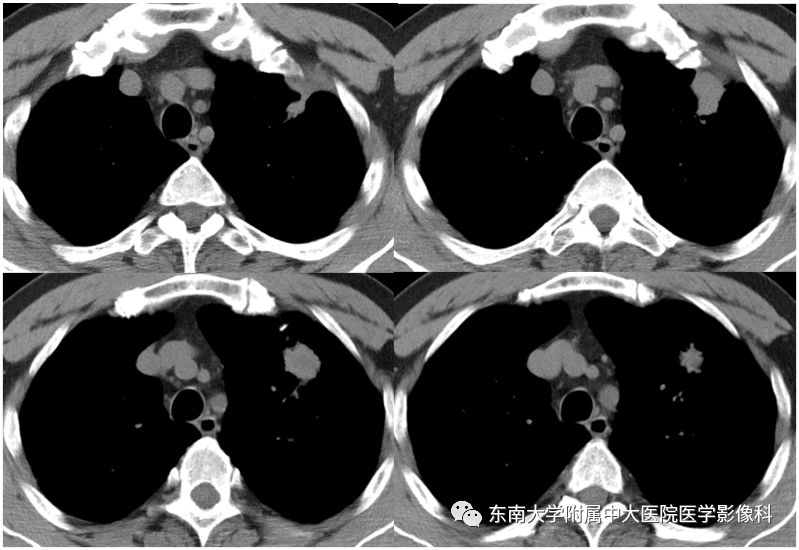

男,70岁,因“腹痛2月余,发现胃窦病变9天”入院

病例结果:病例1:机化性肺炎;病例2:肺腺癌